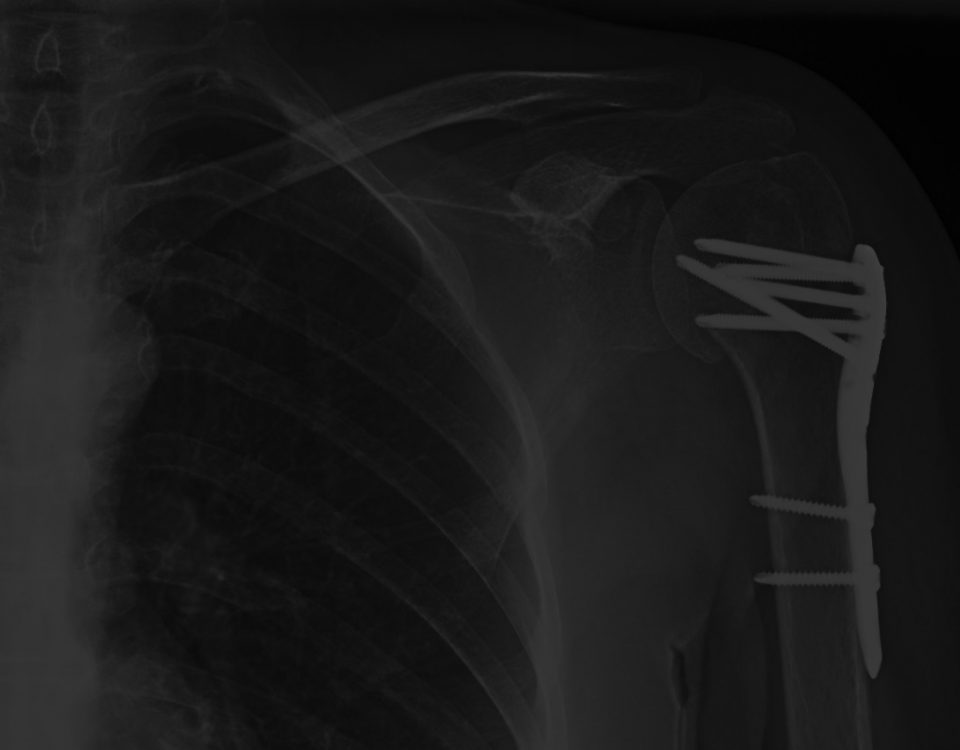

Indemnizacion Fractura De Humero Hombro Luxacion

Indemnización por fractura de húmero

Qué indemnización puedo obtener por una fractura de húmero en un accidente de tráfico? El artículo de hoy, vamos a ver una lesión habitual en accidente […]